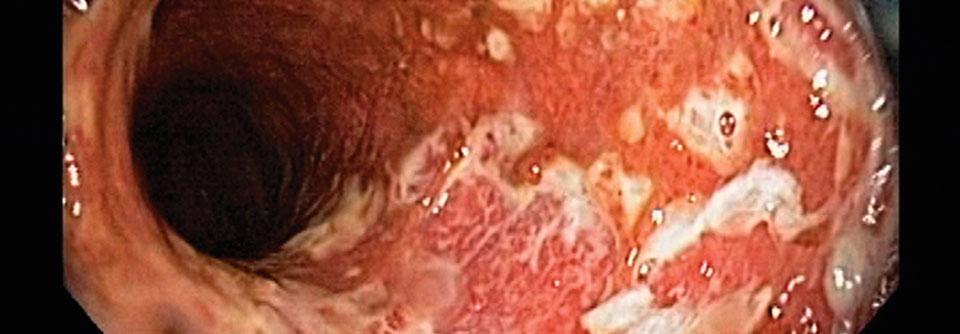

Bei Colitis ulcerosa führt eine Antibiotikatherapie mit anschließendem Mikrobiomaustausch via Stuhltransplantation möglicherweise zur Remission der entzündlichen Darmerkrankung.

Patienten mit aktiver Colitis ulcerosa profitieren möglicherweise von einem oral verabreichten Stuhltransplantat. Der Mikrobiomtransfer im Anschluss an eine Antibiotikatherapie steigerte in einer placebokontrollierten Doppelblindstudie die Remissionsrate.

Nach dieser Induktionsphase zeigte sich ein signifikanter Unterschied: Mit bakterieller Nachhilfe erreichten 53 % der Patienten eine steroidfreie klinische Remission nebst endoskopischer Verbesserung oder Abheilung. Bei den Kontrollen gelang dieser Schritt nur in 15 % der Fälle, so die Autoren.